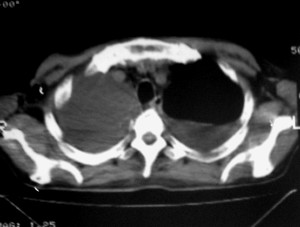

m ,60岁,右上肺ca术后一月。

右侧肺癌术后:肝内可见多个大小不等的低密度结节影。腹腔及双侧胸腔大量积液。考虑:肺癌并胸膜及肝脏转移。

纵隔淋巴结增大,双侧胸水。考虑术后残留,而非复发。

腹水,肝及右肾多发低密度影。考虑转移。

肝及右肾转移瘤,双侧胸水